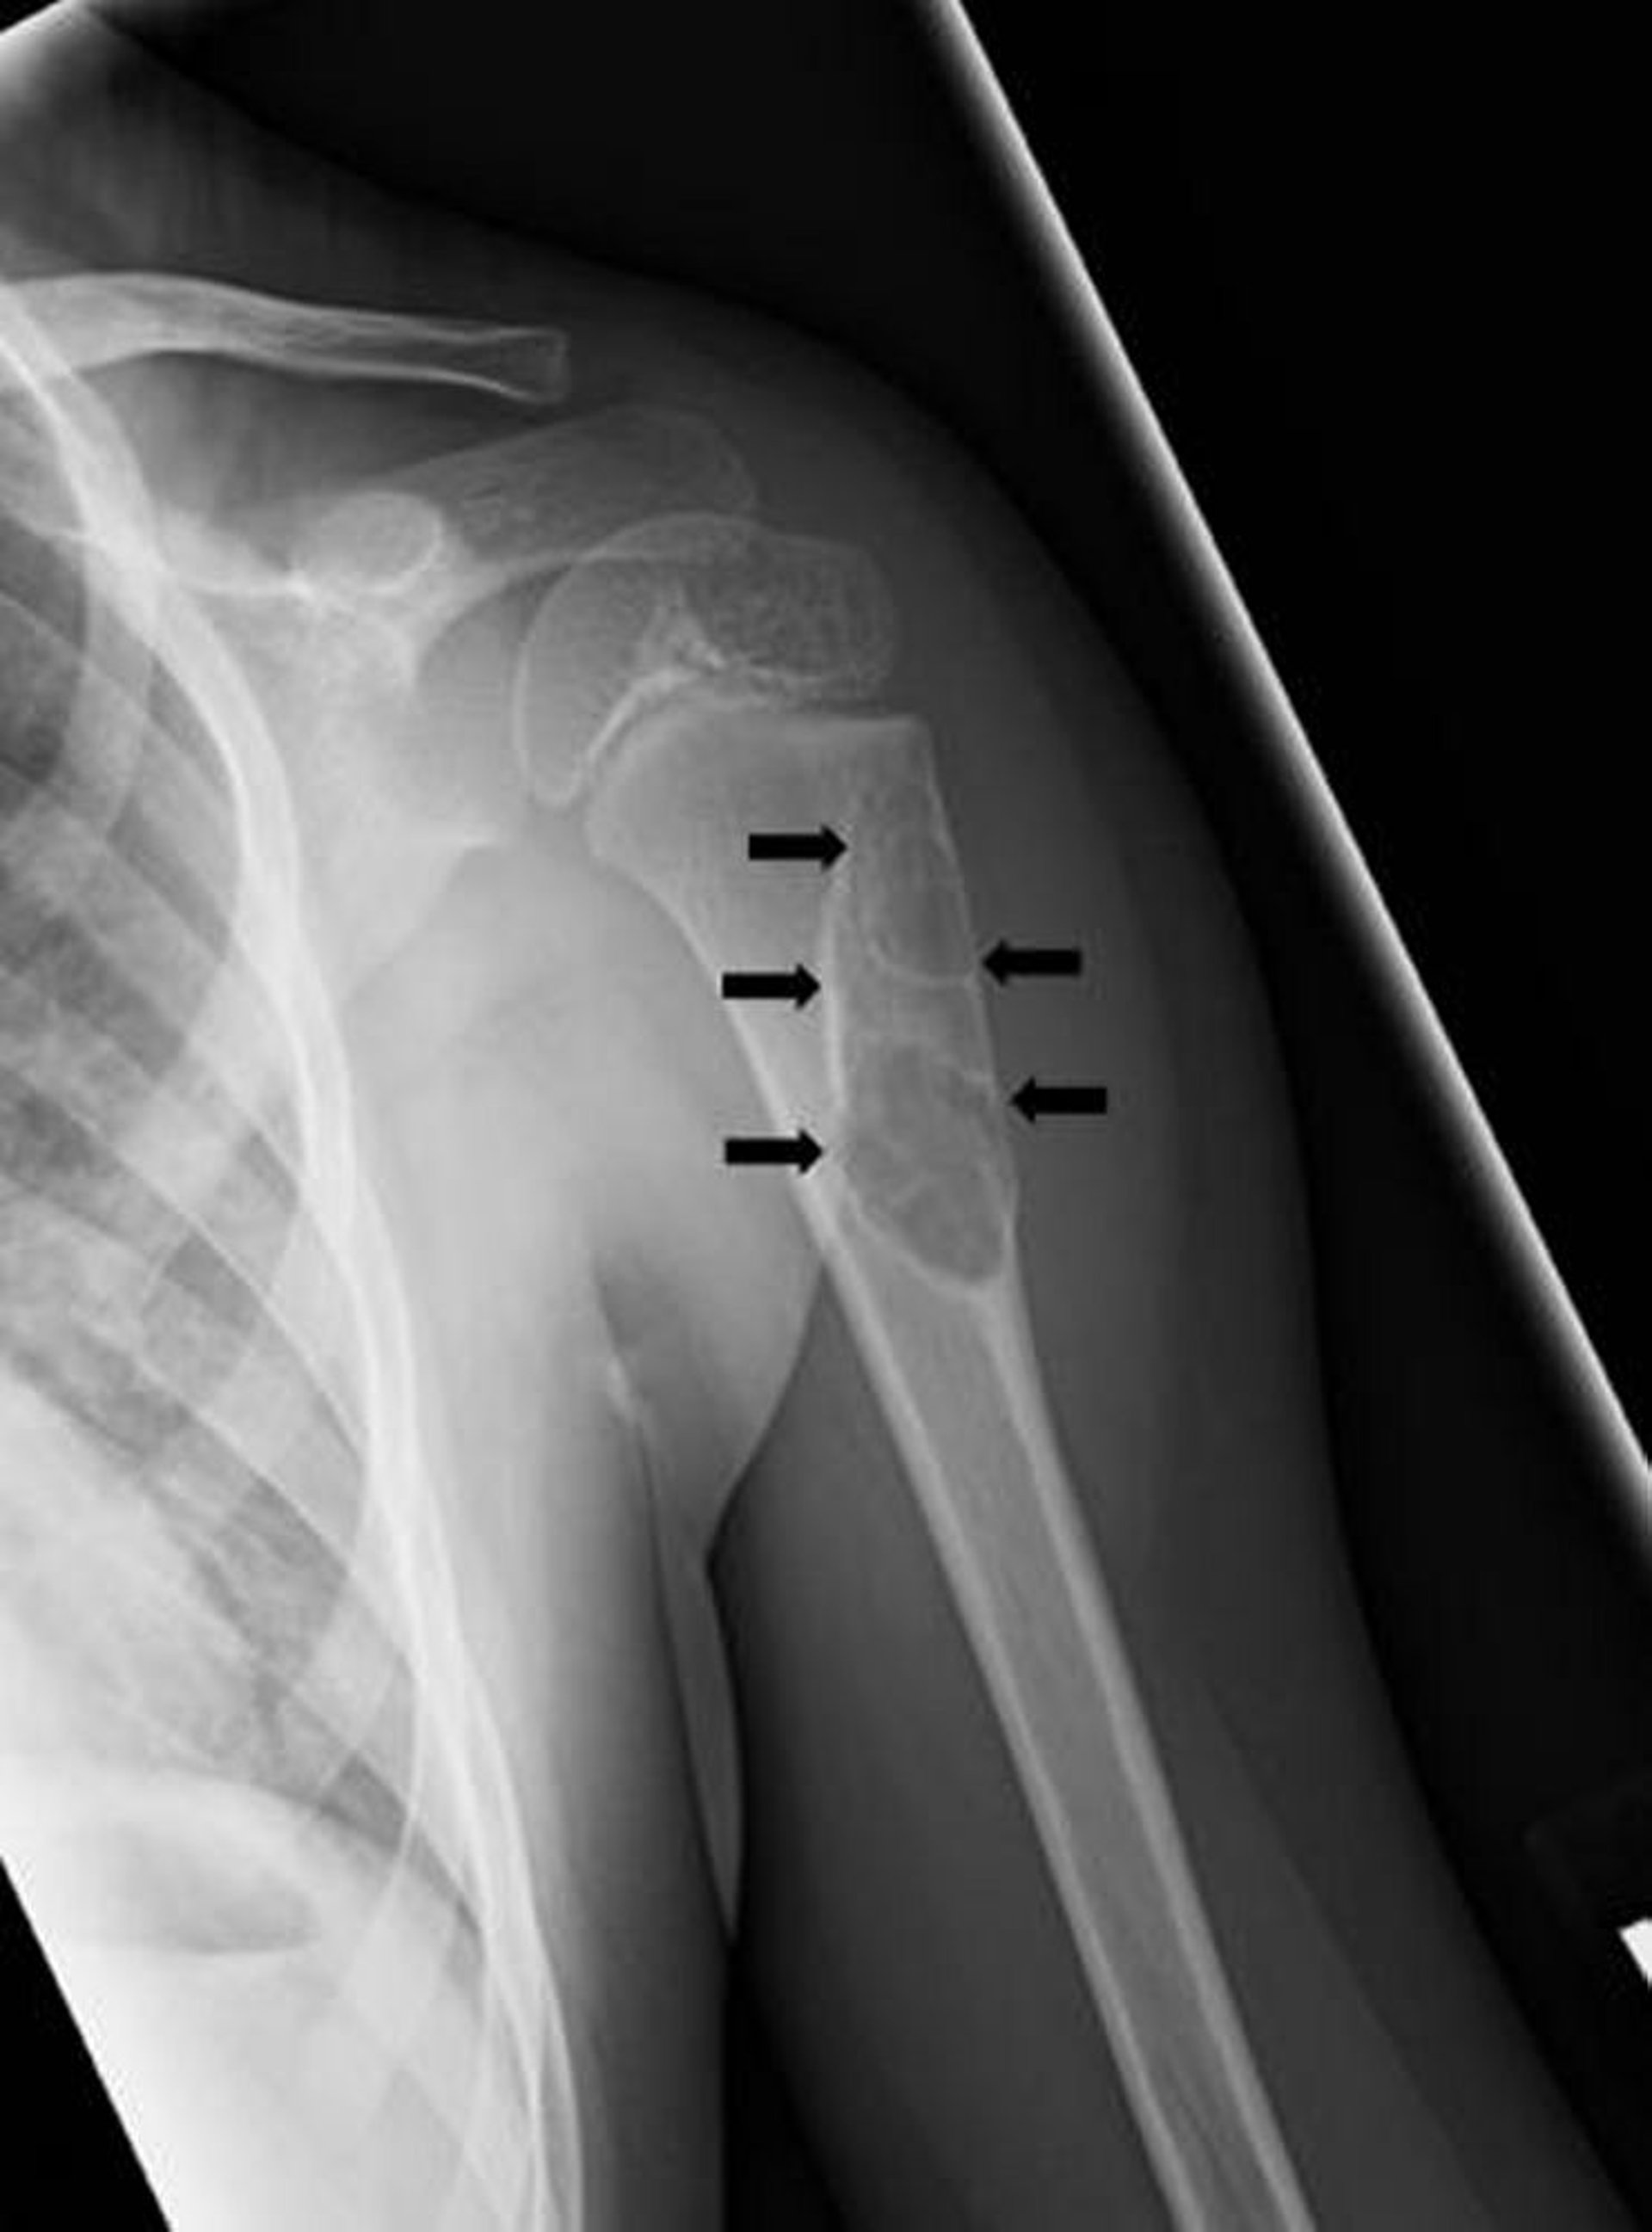

Quiste óseo unicameral

Esta radiografía muestra una lesión quística (flechas) en el húmero de un niño, compatible con un quiste óseo unicameral.

Image courtesy of Michael J. Joyce, MD, and Hakan Ilaslan, MD.